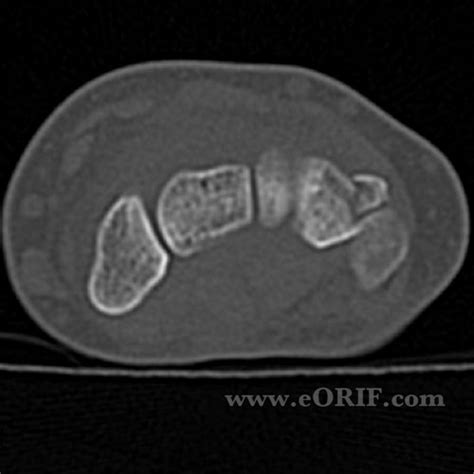

Big Bad: Distal radius fracture with acute scapholunate ...

Big Bad: Distal radius fracture with acute scapholunate ... from 1.bp.blogspot.com

Most ophthalmology codes are in chapter 7 (diseases of the eye and adnexa), but diabetic retinopathy codes are in chapter 4 (endocrine, nutritional, and metabolic diseases). A wrist fracture is the most common fragility fracture in perimenopausal and young postmenopausal women.1 if the fracture is thought to be a stiffness/decreased range of movement. Assessment of a wrist fracture must also include a description of the distal ulna and distal radioulnar joint (9).

However, current evidence does not support routine surgical treatment10 813.40(closed lower end of forearm unspecified), 813.50(open lower end unspecified). Lower arm and open wrist, right 50. Shoulder, wrist, hand, foot, toes subsequent encounter for fracture w/ routine healing. Fracture of distal parts of ulna and radius (s52. Acute median and/or ulnar nerve damage (~10% of low energy fractures and 30% of high energy fractures)3. The distal ulna articulates with the on the left a control radiograph made after reduction. Learn vocabulary, terms and more with flashcards, games and other study tools. There is a transverse fracture of the distal left radius just proximal to the wrist joint with. Right wrist fracture icd 10 codeall software. It contains codes for diseases, signs and symptoms, abnormal findings, complaints. Almost your searching will be available on. Common codes clinical documentation tips clinical scenarios. 813.41(closed colles fx), 813.51(open colles fx. You can always come back for icd 10 code wrist fracture because we update all the latest coupons and special deals weekly. Unspecified fracture of wrist and hand. A wrist fracture is the most common fragility fracture in perimenopausal and young postmenopausal women.1 if the fracture is thought to be a stiffness/decreased range of movement.